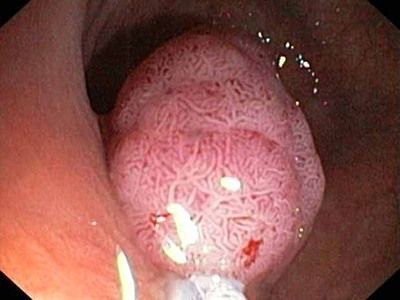

Наприклад, хронічний гастрит або виразкова хвороба можуть призвести до появи запальних змін в шлунковій стінці, що можуть бути передраковими утвореннями. Неусунення запорів або діареї може призвести до пошкодження слизової оболонки кишечника та збільшити ризик розвитку раку кишечника.

Більшість симптомів раку кишечника проявляються досить явно, і їх важко не помітити. У пацієнтів із цим захворюванням на початковій стадії часто з'являються:

- закрепи;

- сильне газоутворення та метеоризм ;

- печія;

- кислотний рефлюкс;

- проблеми із ковтанням;

- нудота блювота;

- діарея та часті симптоми розладу шлунка.